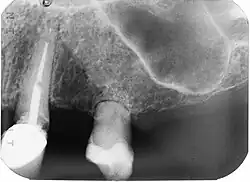

![]() | |

| Post traumatic External tooth resorption 9 | |